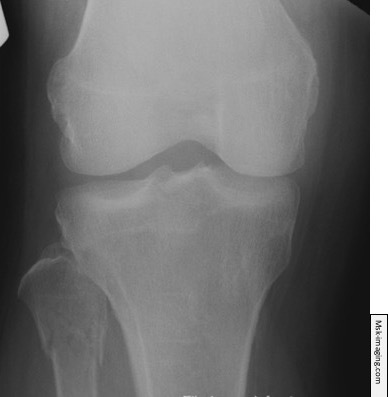

What findings would be consistent with a nerve injury associated with this fracture?

The abnormalities in these X-rays are typical of which condition?